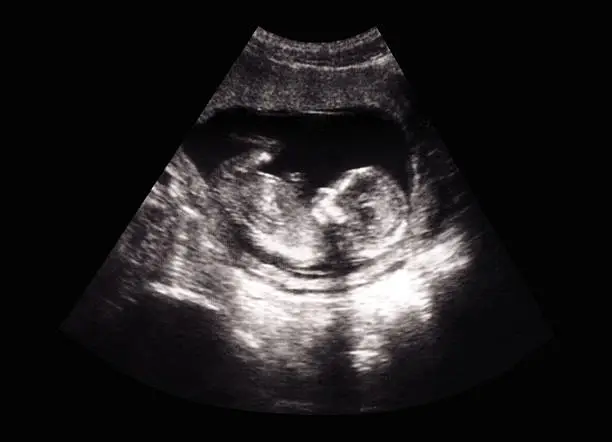

착상혈은 배란 후 수정된 난자가 자궁 내벽에 착상하는 과정에서 발생할 수 있는 출혈로, 이는 보통 배란 후 6일에서 12일 사이에 나타납니다. 수정란이 자궁벽에 자리 잡는 과정에서 자궁 내막의 일부가 손상되면서 소량의 출혈이 발생하게 되는 것입니다. 이 출혈은 보통 연한 분홍색이나 갈색을 띠고, 매우 가벼운 양으로 나타나며 길게는 며칠 정도 지속될 수 있습니다. 하지만 모든 여성들이 착상혈을 경험하는 것은 아니며, 개인에 따라 착상혈의 양상은 매우 다양하게 나타날 수 있습니다.

임신 초기의 hCG 호르몬 분비는 착상이 완료된 후부터 시작되며, 이 호르몬은 임신 여부를 감지하는 데 중요한 역할을 합니다. 그러나 착상혈이 발생한 즉시 hCG 수치가 급격히 증가하지 않기 때문에, 착상혈이 발생했다고 하더라도 임신 테스트기에서는 한 줄이 나올 수 있습니다. 이는 임신 테스트기가 소변에서 hCG 수치를 감지해야만 임신을 확인할 수 있기 때문입니다.